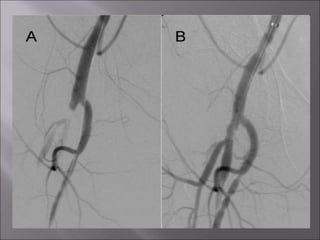

Treatment: Endovascular surgery • Percutaneoustransluminal angioplasty (PTA). • Intravascular stents , and covered stents. •Catheter directed thrombolysis. •Mechanical atherectomy catheters. •Excimer laser. •Drug eluting baloons and stents. (paclitaxel)

 It iscontrolled fracture of the atheromatous plaque ,and pushing it to the periphery of the artery by the balloon inflation, thus creating a space in the artery center.

 Limitations ofendovascular  High re-occlusion rate in long lesions.  Guide wire can fail to cross highly calcific chronic total occlusion (CTO). WWW.SMSO.NET

 Progression ofthe original disease . Prevention by controling the risk factors and immuno modulation of autoimmune diseases  Intimal hyperplasia Reaction to mechanical manipulations or barotrauma to the wall of an artery that causes migration of myoepithelial cells from the media to the sub-intima with proliferation that causes sub-intimal tissue growth with narrowing of the arterial wall . Prevention by drug eluting balloons or stents.